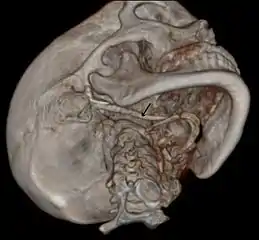

In vascular Eagle syndrome, the elongated styloid process comes in contact with the internal carotid artery below the skull. In these cases, turning the head can cause compression of the artery or a tear inside the blood vessel, which restricts blood flow and can potentially lead to a transient ischemic attack or stroke.[5] Sometimes, compression of the internal jugular vein can also occur and might lead to increased intracranial pressure.[7][8][9]

Imaging is important and is diagnostic. Visualizing the styloid process on a CT scan with 3D reconstruction is the suggested imaging technique.[12] The enlarged styloid may be visible on an orthopantogram or a lateral soft tissue X ray of the neck.